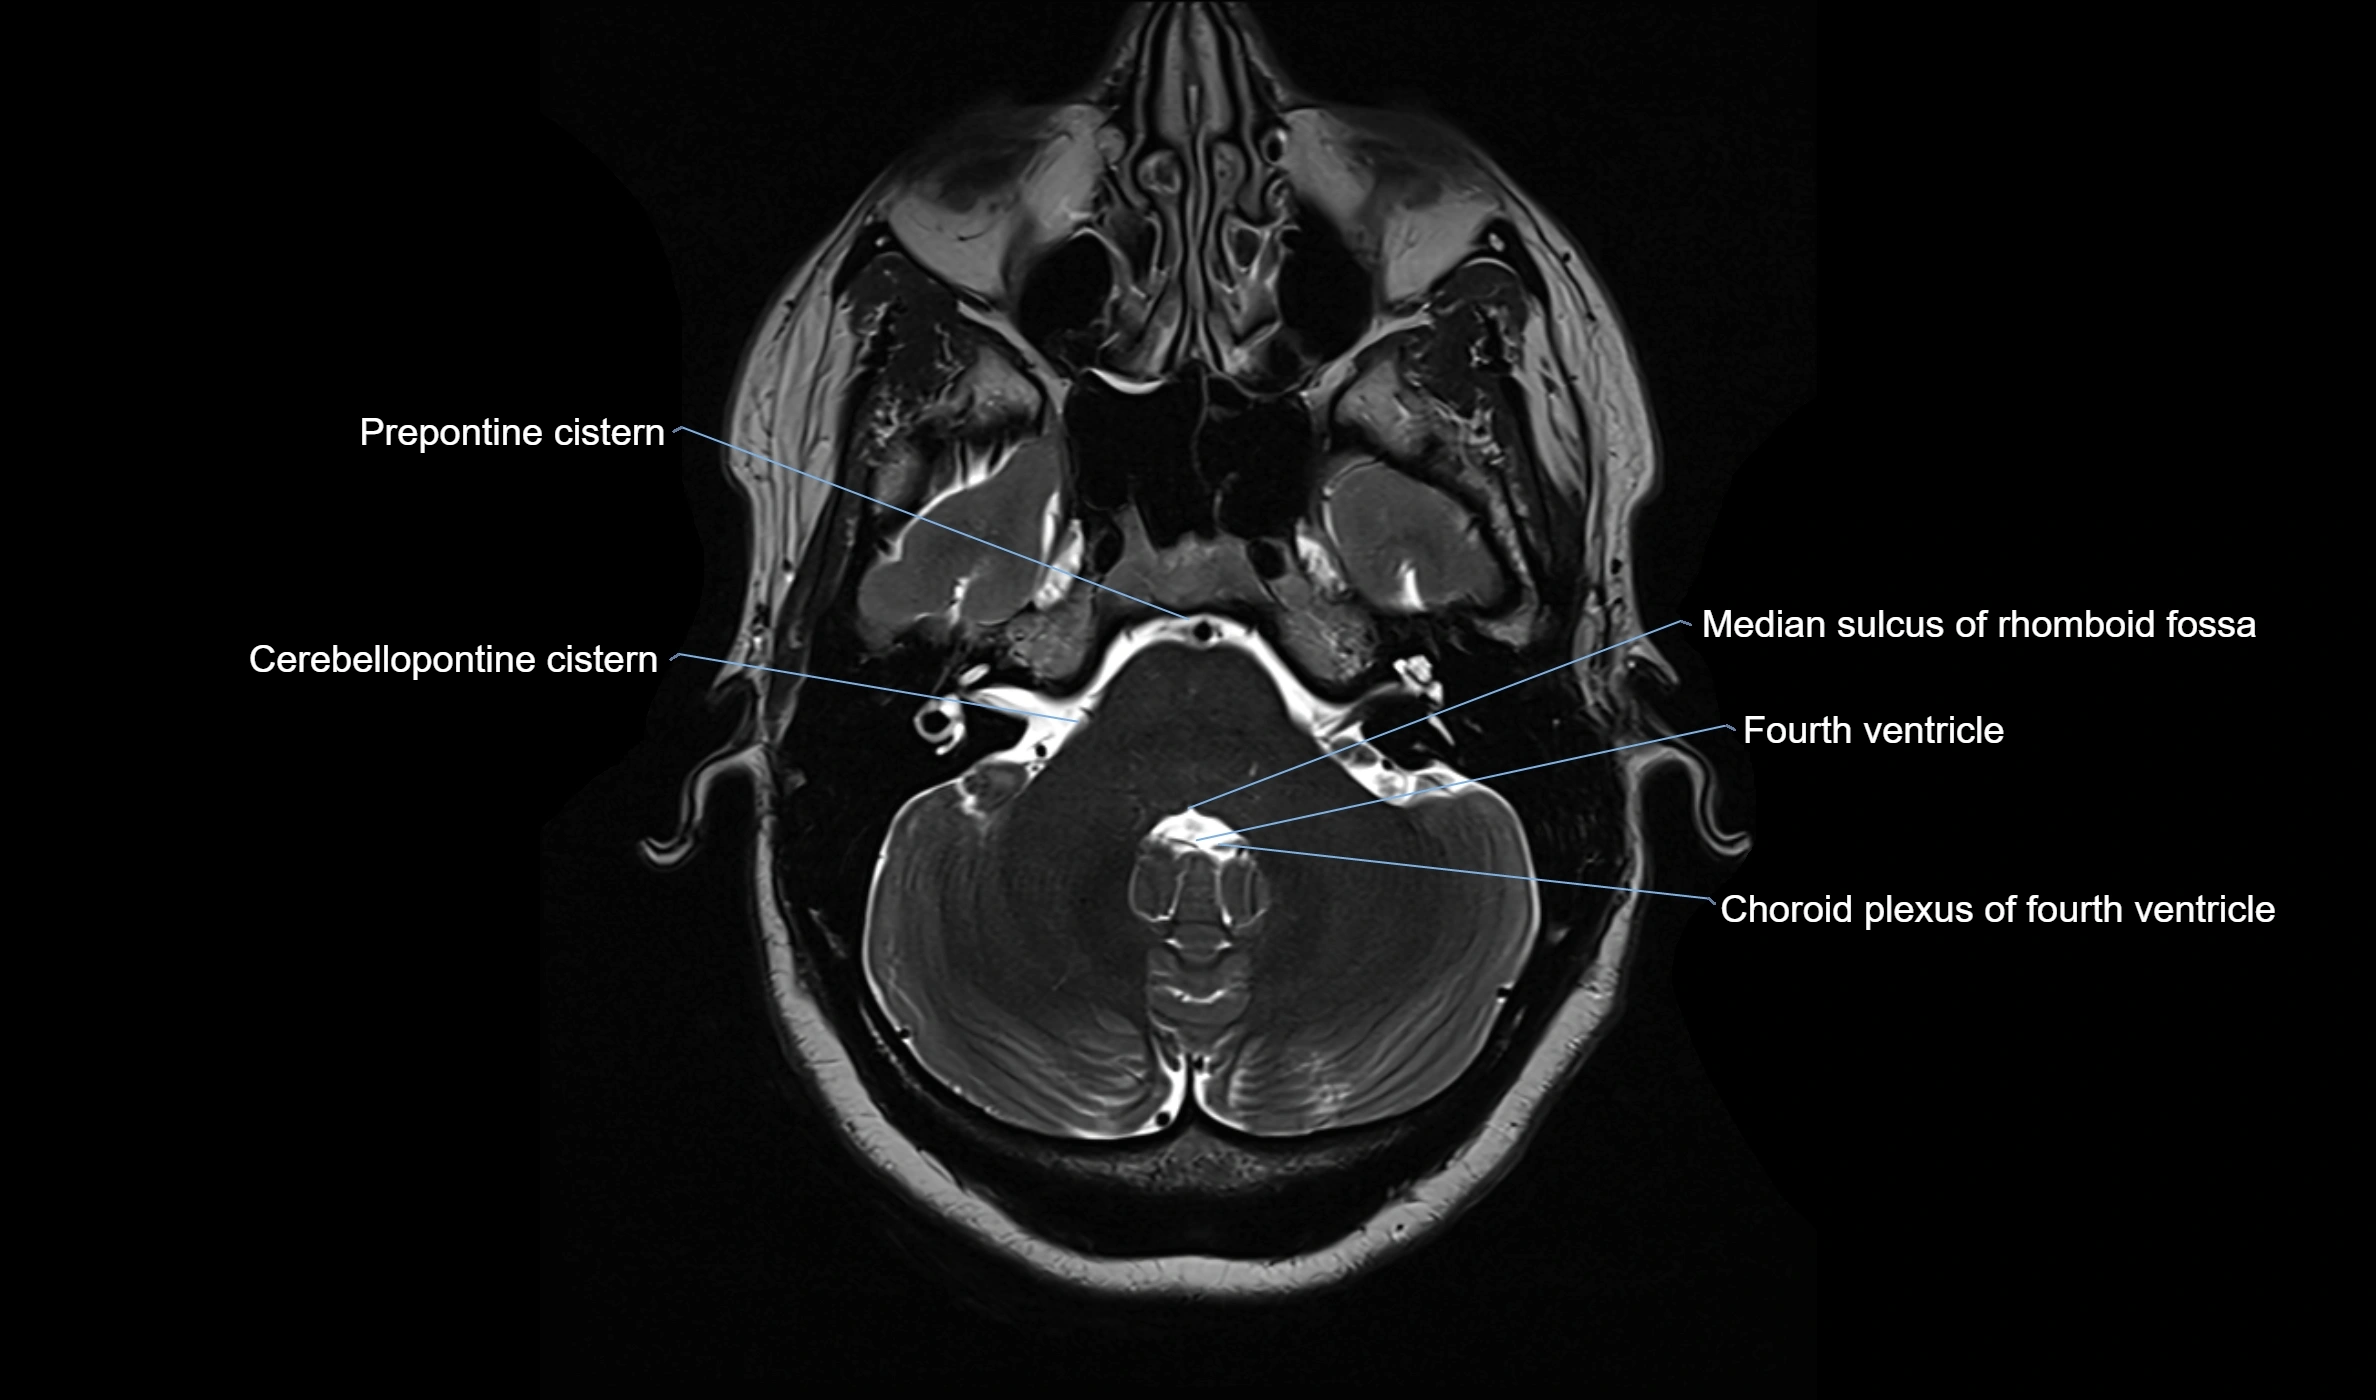

CT image

image